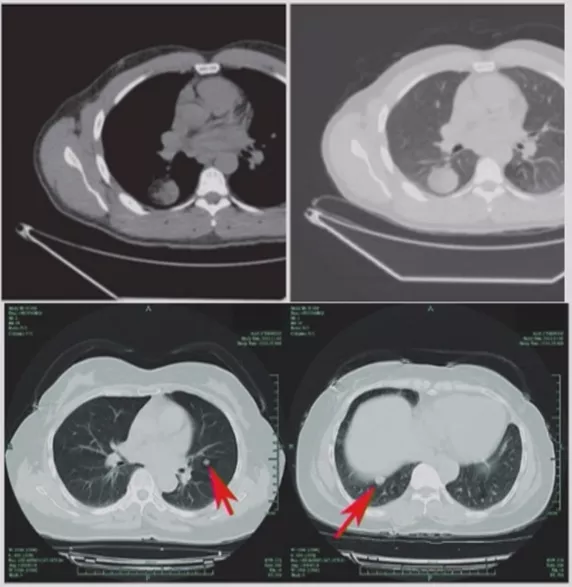

非手术活检的局限性

但是非手术活检获取的标本都是小标本,所以取标本有限。如果病理报告基于针尖大小的组织样本,那就存在许多不确定性。上图所示,是我们的一个病例,4月21日,外院CT引导下经皮肺穿刺,我院病理会诊为慢性炎症;5月16日入院,我建议再做一次活检,于是5月19日经皮肺穿刺,病理提示还是慢性炎症;两次病理提示均为慢性炎症,但是完全用慢性炎症解释这个肺结节还有些疑问,我建议再做一次经皮肺穿刺,6月7日第三次活检的病理结果提示为中分化腺癌,而且基因检测提示ALK阳性,是黄金突变,靶向治疗效果很好。因此,我们取小标本的时候,要慎重解释阴性结果。